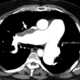

Chronic pulmonary disease

Respiratory diseases, or lung diseases, are pathological conditions affecting the organs and tissues that make gas exchange difficult in air-breathing animals. They include conditions of the respiratory tract including the trachea, bronchi, bronchioles, alveoli, pleurae, pleural cavity, and the nerves and muscles of respiration. [Source: Wikipedia ]